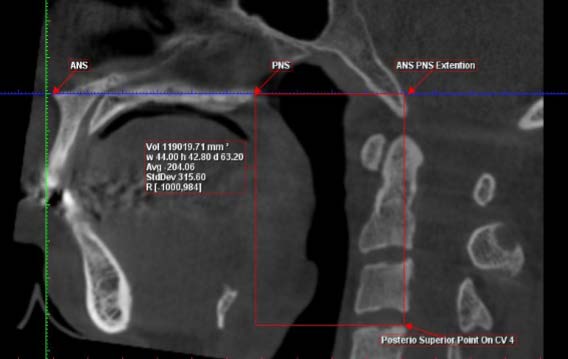

The airway could be isolated after demarking the total volume of interest required for the study. The ROMEXIS software automatically created the third dimension based on the height and the width of the region marked in the two-dimensional view (Figure : 2). Using the 3D region growing tool, the 'air cavity' was selected from the pre-sets. A local threshold level of 70 was used and the particular area of interest in the airway region was selected. This procedure was carried out by a single operator (S.K) to create and measure the rendered volumes. For reliability purpose, it was repeated by the same operator after a period of two weeks and finally, the average is taken for the calculation.